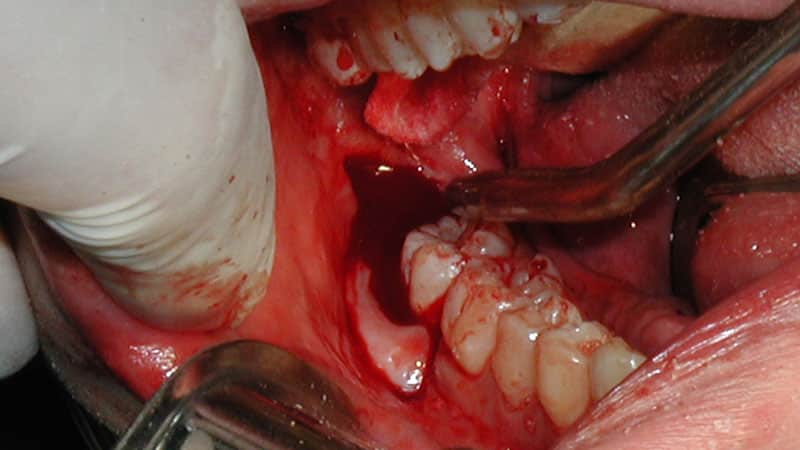

Процесс удаления восьмого зуба на нижней челюсти изображен на фотографии выше.

Во время сложного удаления зубов мудрости, хирург использует специальный инструмент, делает надрезы и затем зашивает раны. Эта операция часто выполняется на зубах, которые не могут правильно вырасти или находятся в горизонтальном положении. Врачу приходится удалить кость, чтобы достать зуб и его корни.

Операция проводится в хирургическом кабинете с использованием сильных обезболивающих средств. Все необходимые антисептические меры принимаются, чтобы обеспечить стерильность помещения. Через три дня рана зашивается рассасывающимися нитями, которые удаляются после заживления раны.